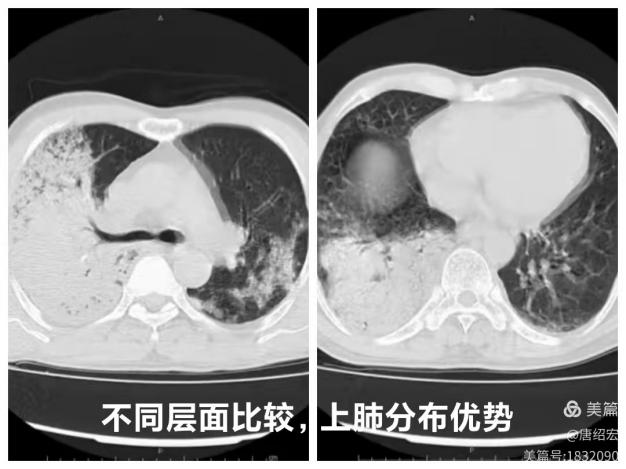

2.  右肺上叶尖段是否占据整个层面?

肺炎链球菌肺炎多为肺泡性肺炎,少数血播肺炎链球菌肺炎好发于老年人及免疫力低下人群,PCT 明显增高。影像上,早期在血管炎的基础上仍能见到按肺小叶充填及闲置的表现(肺泡性肺炎的表现),而大片实变影已不能分辨是否为血管炎(病灶边缘磨玻璃仍可看出血管炎),在肺尖段不会占据整个层面(与铜绿假单胞菌肺炎不同),而在下肺往往表现为齐头并进的特点,分布上多上肺优势。